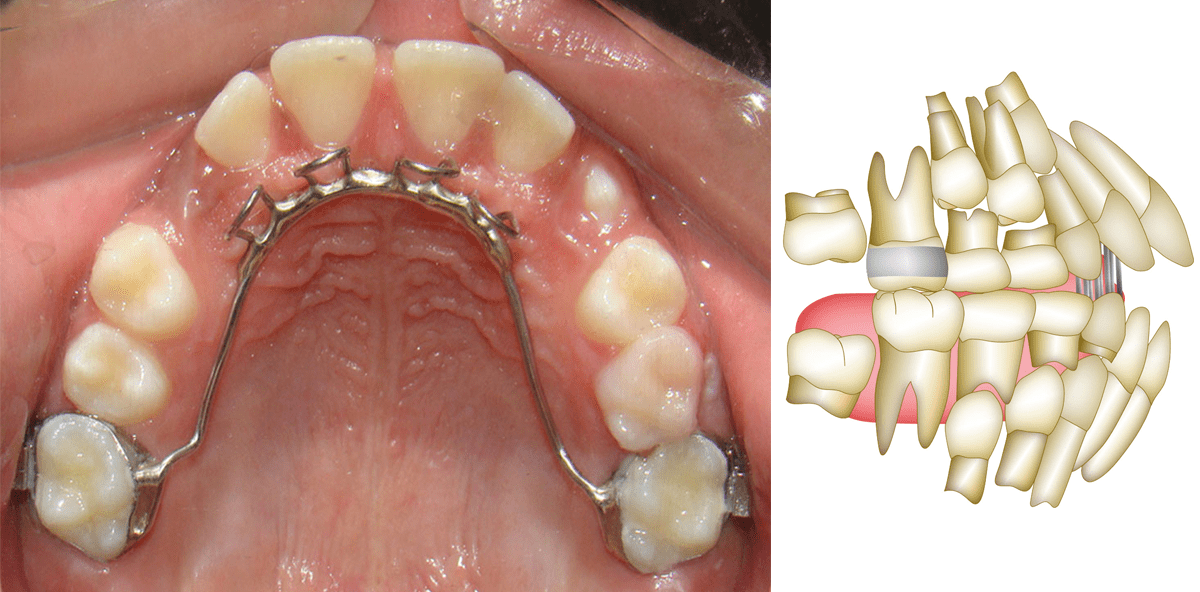

3. Begleitende Verwendung einer Gaumenklammer oder von Zungenspornen während der Behandlung

Die Gaumenklammer beseitigt anhaltende schädliche orale Gewohnheiten sowie das Stoßen und die Positionierung der Zunge zwischen den Frontzähnen (Abb. 4).11,17 Dies verbessert die Effizienz der Behandlungsmechanik mit den Gummizügen, indem die Faktoren beseitigt werden, die das Schließen des Bisses verhindern. Die Zungensporne haben eine ähnliche Wirkung und konditionieren die Zunge dazu, eine weiter hinten gelegene Ruhestellung einzunehmen. Da anormalen Muskelfunktionen beim Wiederauftreten eines offenen Bisses als wichtige Faktoren angesehen werden, hilft die Verwendung dieser Apparaturen, die Muskelfunktion begleitend während der Behandlung zu korrigieren und somit zur Verbesserung der Stabilität der Behandlung eines offenen Bisses beizutragen.

4. Aktive Retention

Eine aktive Retention kann entweder während oder nach der Behandlung durchgeführt werden (Abb. 5 und 6).16 Während der Behandlung müssen die intermaxillären anterioren Gummizüge, nachdem der Biss damit geschlossen wurde, weiterhin vier Monate lang 18 bis 20 Stunden pro Tag verwendet werden, um die Knochenbildung in der Alveole zu ermöglichen. Nach diesem Zeitraum wird eine zusätzliche Frist von durchschnittlich acht Monaten mit weiterer Verwendung der Gummizüge empfohlen. Der Umfang der täglichen Verwendung der Gummizüge wird in dieser Frist nach und nach reduziert. Nach der Behandlung kann ein modifizierter Hawley-Retainer mit Zungenklammer und posterioren Bite Blocks verwendet werden. Durch die Zungenklammer wird ein Vorstoßen und die Positionierung der Zunge zwischen den Frontzähnen verhindert. Die posterioren Bissblockaden beschränken die vertikale Entwicklung der posterioren Zähne, was beitragende Faktoren für ein Wiederauftreten eines offenen Bisses bei heranwachsenden Patienten sind. Auch wenn Einigkeit besteht, dass die aufgeführten Verfahren die Behandlungsstabilität erhöhen, müssen sie immer noch untersucht werden.